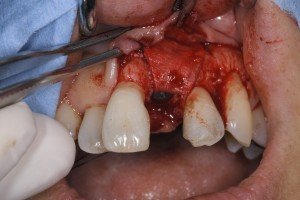

切開線は、審美領域から外して犬歯の遠心に設定し、三角弁にてフラップをあけました。

インプラント埋入後に裂開が生じました。

オペ終了時の所見です。